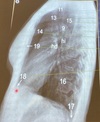

Que estructura anatómica esta en el numero 11

Traquea

Que estructura anatómica esta en el numero 13

Vasos supra aórticos

Que estructura anatómica esta en el numero 15

Espacio retro traqueal

Que estructura anatómica esta en el numero 9

Cayado aórtico

Que estructura anatómica esta en el numero 14

Espacio aéreo retro-esternal

Que estructura anatómica esta en el numero 19

Esternón

Que estructura anatómica esta en el numero 18

S.Cardiofrenico